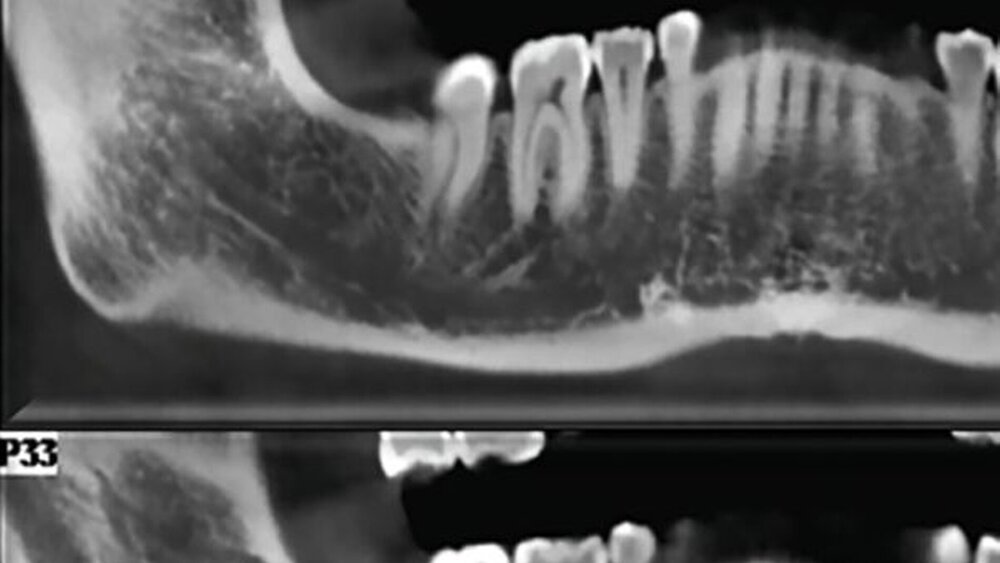

In der sagittalen Ebene des DVTs zeigte sich „eine kleine, wenig diffuse Röntgenopazität in der Nähe des Unterkieferwinkels sowohl auf der medialen als auch auf der lateralen Fläche […]. Die PET-Ergebnisse zeigten eine Fluor-2-Desoxy-D-Glucose-Aufnahme im linken Winkelbereich des Unterkiefers.“ Es wurde im Anschluss eine Feinnadelaspirationszytologie durchgeführt, die Merkmale eines metastasierenden Mammakarzinoms ergab. Differenzialdiagnostisch kam hier auch eine Osteonekrose aufgrund der Bisphosphonatbehandlung in Frage. Die Patientin wurde zurück an ihren Onkologen verwiesen.